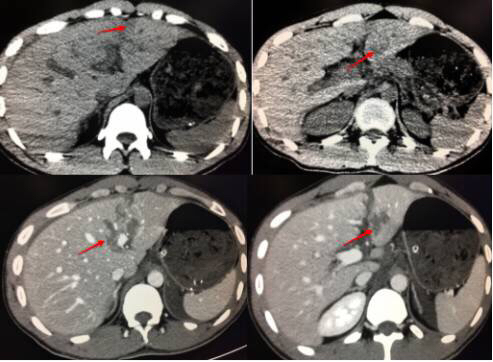

22岁小男生,跟朋友比赛转呼啦圈,出现左上腹痛,以为是转多了胃肠不好,没留意。随后疼痛难忍,到医院就诊。做了CT竟然脾周少量积液,看到这样表现,一定要怀疑脾破裂,做增强证实了脾破裂诊断。很幸运的是,他这样边缘的撕裂伤,可以保守治疗好转。

1.平扫要注意肝胆胰脾周围有无积液,如果有高密度积液,说明就是积血。很多可能有器官破了,要提示做增强扫描,增强一目了然。

23岁男,车祸入院,平扫很可能漏掉,调节窄窗宽,密度不均匀,增强很明显撕裂伤。

18岁男,车祸入院,平扫脾周积液,高密度,边缘见条状高密度影,脾脏积血(看到此征象,夜班急诊的时候千万要警惕脾破裂,及时提示临床医生,患者随时都有可能大出血休克)。CT增强可见脾破裂,破口及积液显示较平扫清晰。